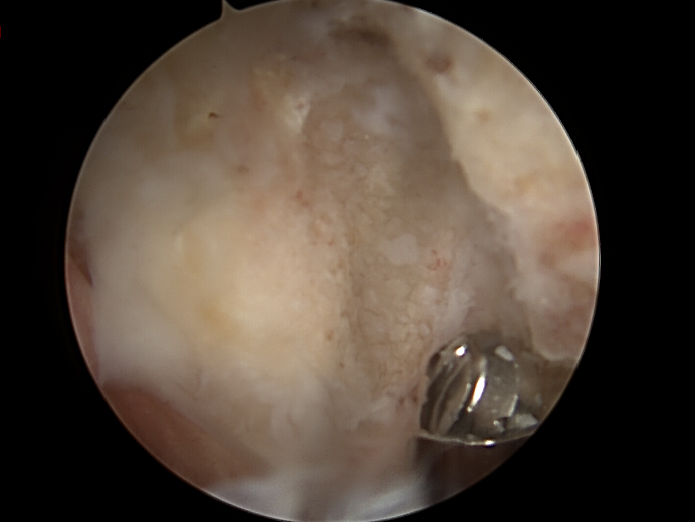

subakromiale dekompression von dr. timmel von ortho-timmel.at

Begleitmaßnahmen und Wundverschluss

• Hautverschluss (Naht oder Klammern).

• Steriler Verband